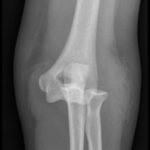

Elbow dislocations are classified by the position of the radio-ulnar joint relative to the humerus.1 Images 1, 2, and 3 show a left posterior elbow dislocation; the radius and ulna are displaced posteriorly with respect to the distal humerus. The lateral view of the elbow most clearly shows this: trochlear notch of the ulna is empty and displaced posteriorly relative to the trochlea. There is no associated fracture. Images 4 and 5 show the elbow status-post reduction, demonstrating proper alignment of the distal humerus with the radius and ulna.